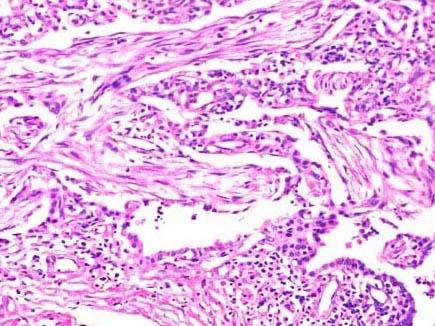

患者,1月前因高热,咳铁锈色痰伴呼吸困难入院。经治疗临床症状消失,但肺下叶实变灶不消失,手术切除,镜检如图所示,正确的诊断是 ( )A.吸入性肺炎...

问题 患者,1月前因高热,咳铁锈色痰伴呼吸困难入院。经治疗临床症状消失,但肺下叶实变灶不消失,手术切除,镜检如图所示,正确的诊断是 ( )

选项 A.吸入性肺炎 B.矽肺 C.肺肉质变 D.肺脓肿 E.肺癌

答案 C